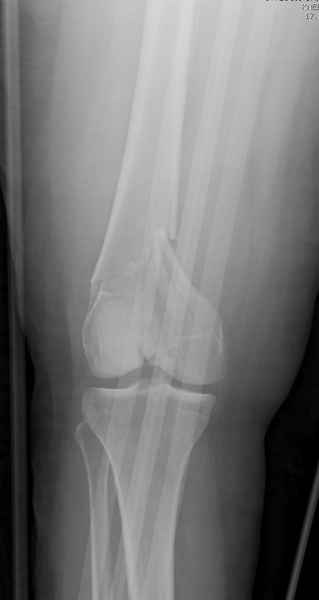

При наличии различных имплантов, любые варианты: слева (полу) открытым - мининвазивным, а справа закрытым интрамедуллярным методом, его считаем более чем приемлемым для фиксации данных переломов.

Проксимальная и дистальная блокировка, независимо от техники введения штифта, ретроградно или антеградно, гарантирует сращение сегментарных переломов бедра без укорочения. Штифты диаметром 12 мм с блокировкой сверху и вниз двумя шурупами выдерживают вес 75 кг больного, что позволяет раннюю профилактику контрактур.

Погоня за "красивой рентгенограммой" не всегда оправдана для фиксации кости, где имеется массивное мягкотканое покрытие. Если так уж хочется исправить положение кости, то при наличии ЭОП, большие костные фрагменты могут быть развернуты или приближены к основному фрагменту методом применения Joystick.

Главное в лечении сегментарных переломов - необходима осторожность при рассверливании канала, продвижение гибкого сверло через сегмент проводят без сверления, толканием, а то были случаи, когда весь сегмент крутился вместе со сверлом.

Из-за вариабельности установки дистальных шурупов и возможности перкутанного введения проксимально предпочитаем DePuy Polyax, хотя на сегодняшнем маркете множеств вариантов фиксации дистального бедра перкутанном методом.